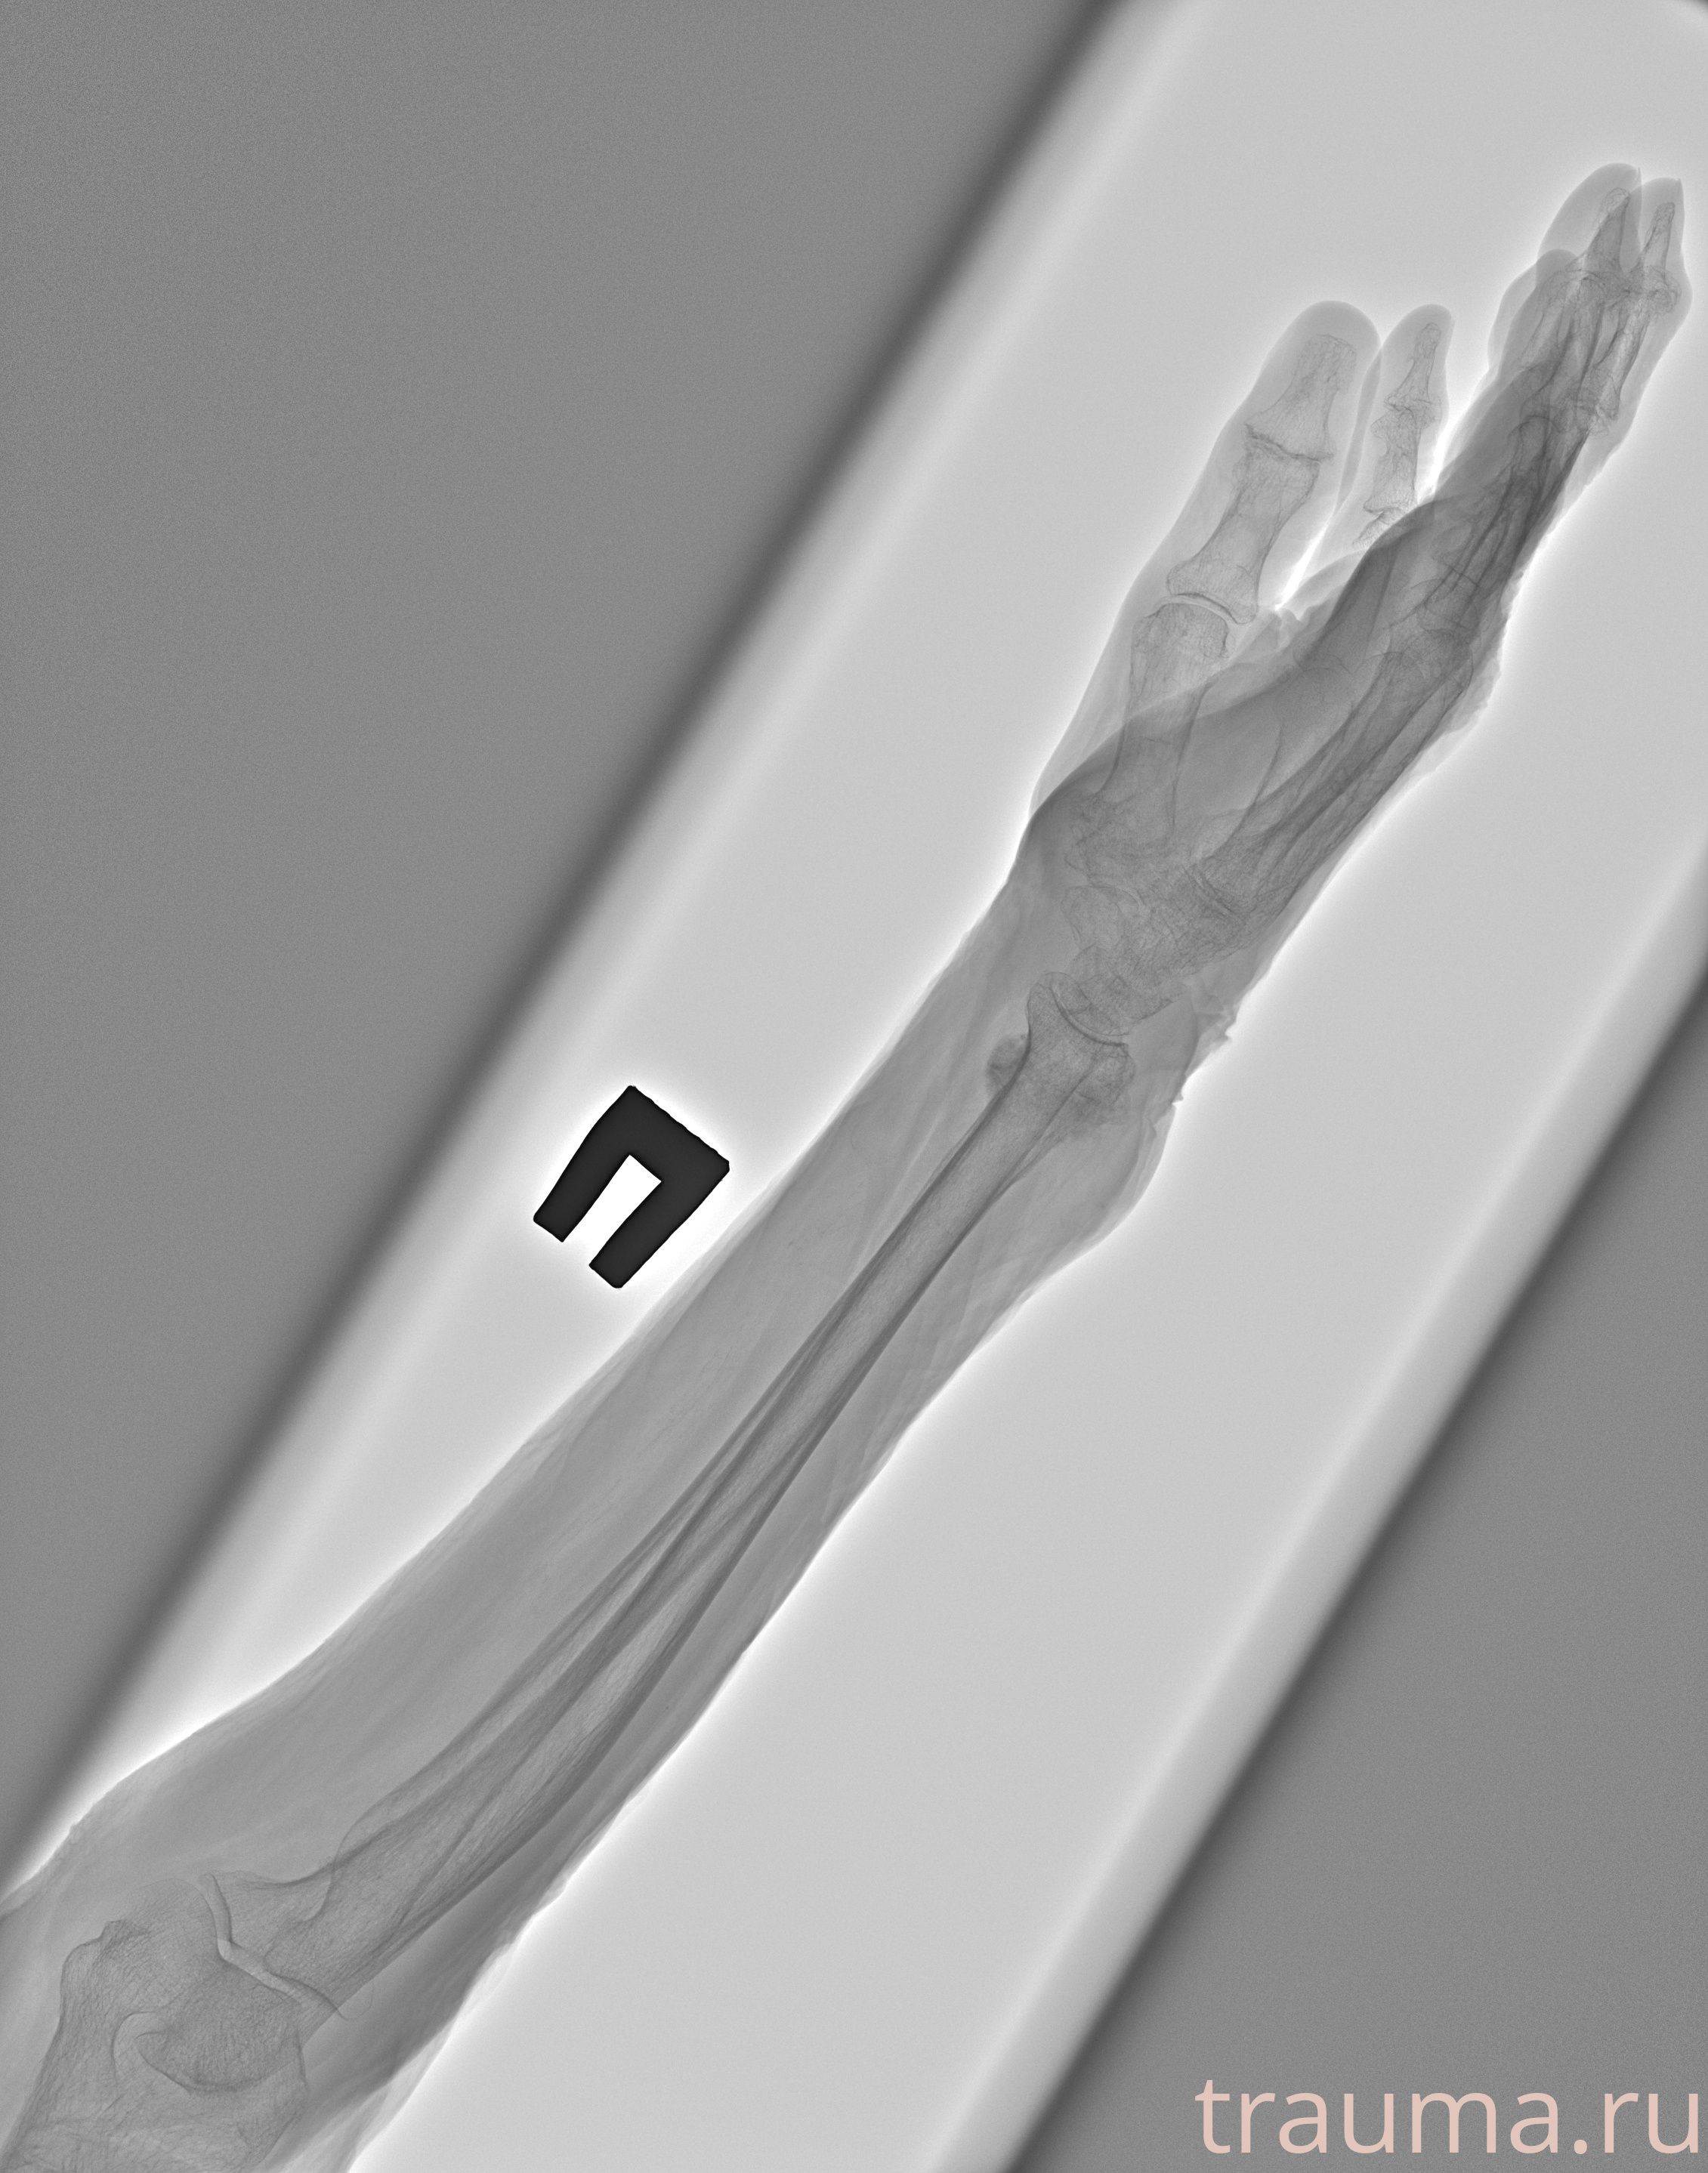

Рентгенограммы

Рентген на дому: по вашему адресу приезжает врач-рентгенолог, травматолог-ортопед с мобильным рентгеновским аппаратом, проводит диагностику травмы или заболевания, делает необходимые рентгенограммы, дает рекомендации по дальнейшему лечению. Получить качественные снимки в домашних условиях возможно благодаря уникальной методике, разработанной МосРентген Центром для института  Склифосовского